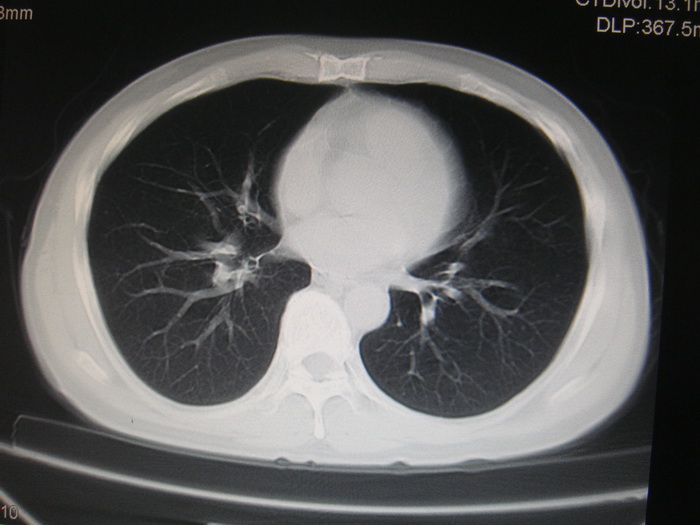

标题: CT28366:男性,45岁,偶尔发现右颈部肿块行胸部CT扫描。 [打印本页]

男性,45岁,偶尔发现右颈部肿块行胸部ct扫描。

两肺多发结节灶及纵膈淋巴结肿大考虑为转移

两肺多发性转移瘤,纵隔淋巴结转移。

两肺多发性转移瘤,纵隔淋巴结转移。食道中上段管壁似乎增厚,作相关检查。

两肺多发性转移瘤,前上纵隔淋巴结转移。